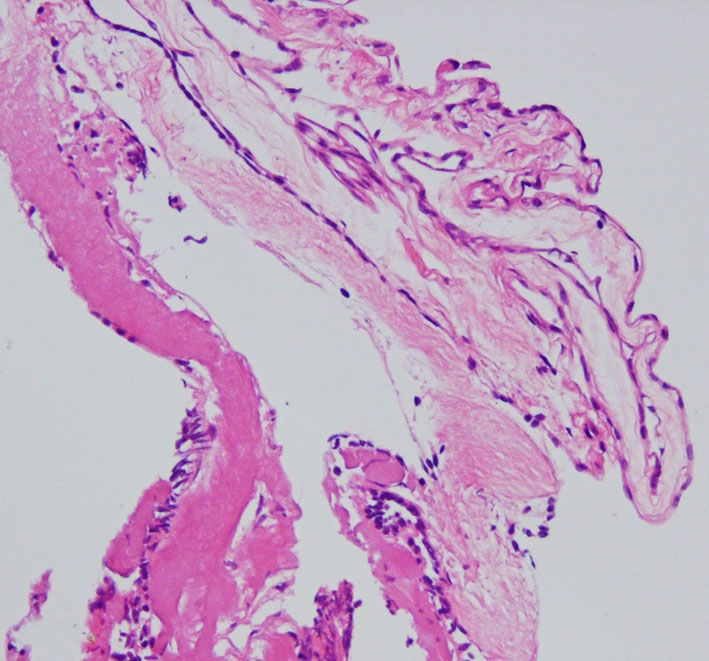

病理

薄い膜を摘出したのでくしゃくしゃになっています